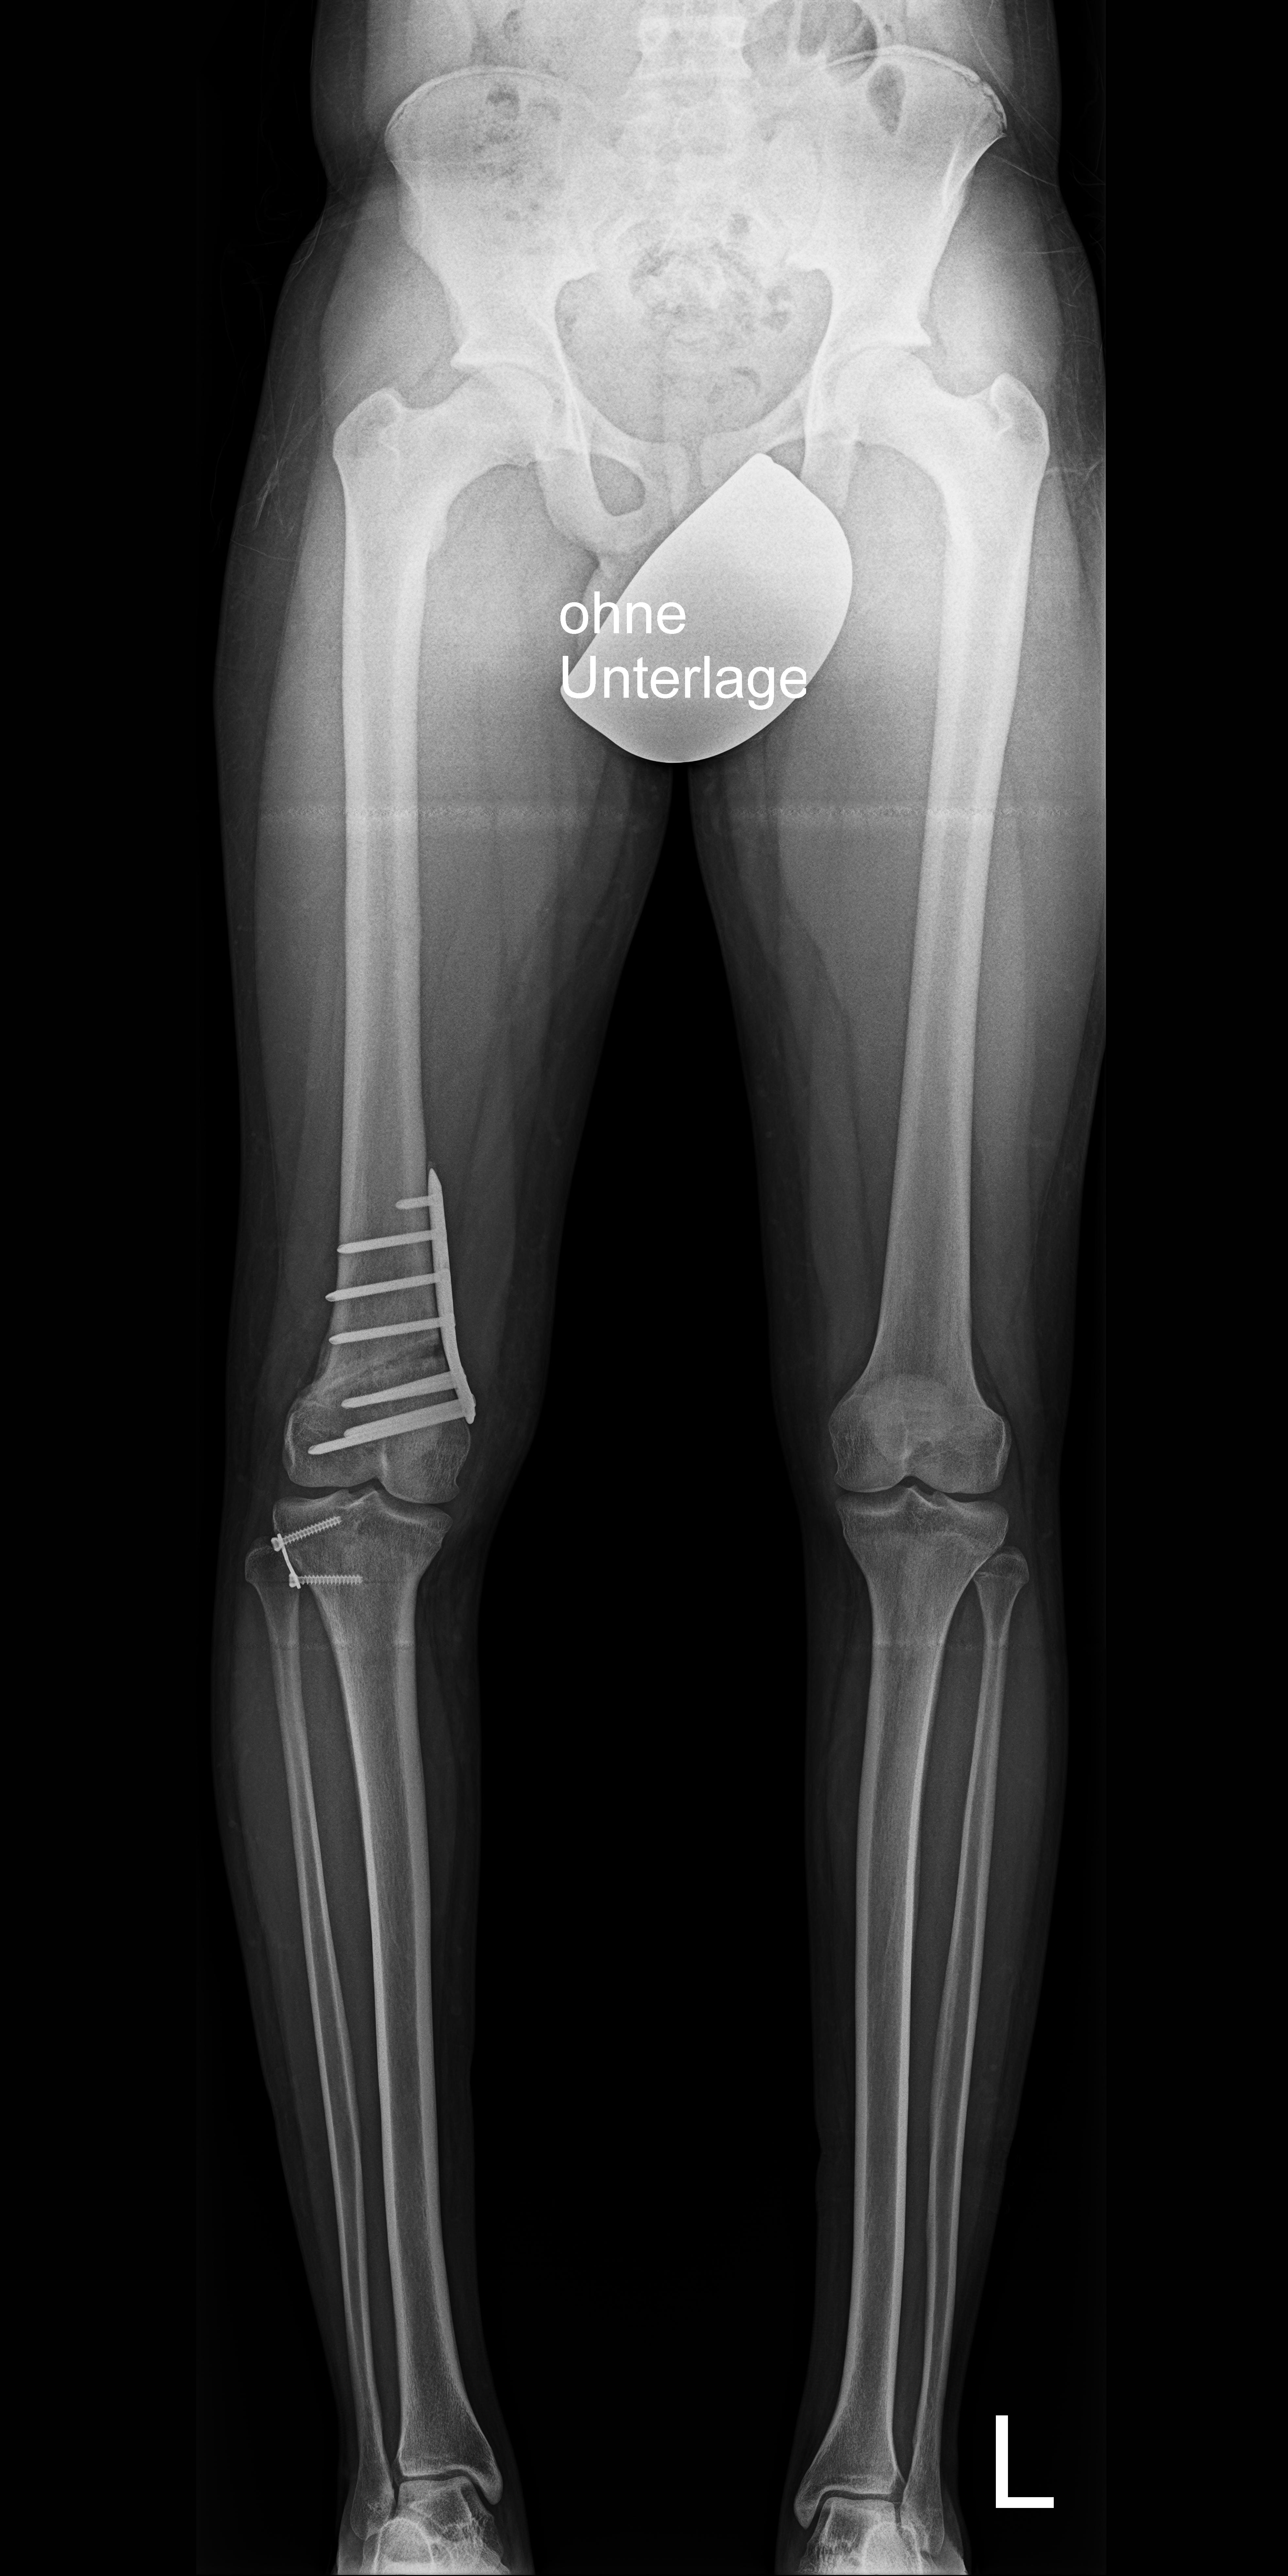

Болезнь Блаунта Фото 115 фотографий